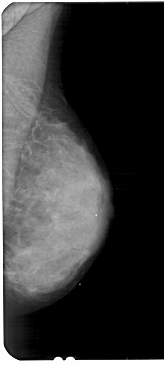

A_1837_1.RIGHT_MLO

RIGHT_CC LINES 4771 PIXELS_PER_LINE 2251 BITS_PER_PIXEL 12 RESOLUTION 43.5 NON_OVERLAY

RIGHT_MLO LINES 5491 PIXELS_PER_LINE 2446 BITS_PER_PIXEL 12 RESOLUTION 43.5 NON_OVERLAY